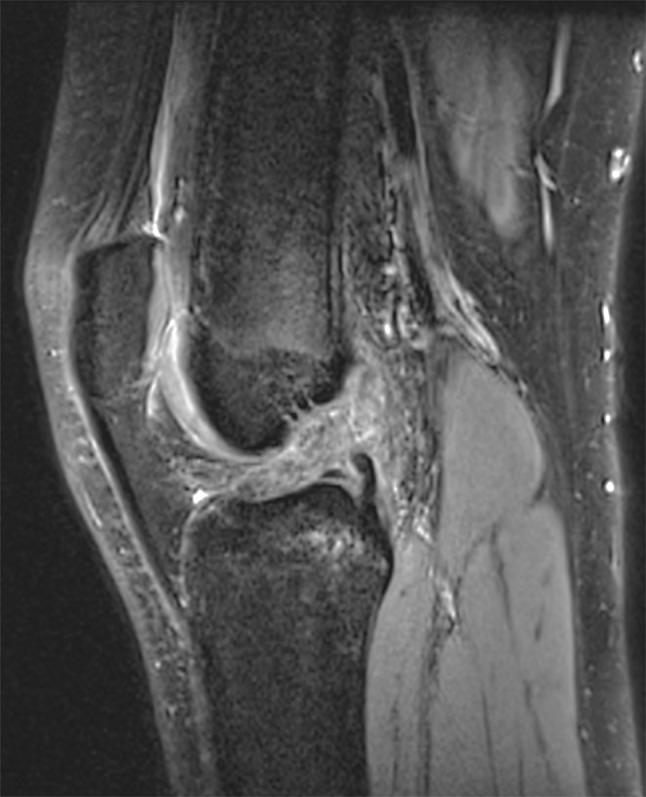

A retrospective review of pediatric patients undergoing knee magnetic resonance imaging (MRI) was performed over a 4-year period. Inclusionary criteria included mid-substance ACL disruption, skeletal immaturity, noncontact injury, without associated ligamentous disruption, and no medical condition associated with ligamentous laxity. MRI studies were analyzed by a pediatric musculoskeletal radiologist, measuring identified bony parameters, and compared with an age-matched control group without ligamentous injury. Data were analyzed using unpaired t-tests and logistic regression.

对4年间接受膝关节磁共振成像(MRI)检查的儿科患者进行回顾性研究。纳入标准包括ACL实质中部断裂、骨骼未成熟、非接触性损伤、无相关韧带断裂,且无与韧带松弛相关的疾病。MRI研究由儿科肌肉骨骼放射科医生进行分析,测量已识别的骨骼参数,并与无韧带损伤的年龄匹配对照组进行比较。数据采用非配对t检验和逻辑回归分析。